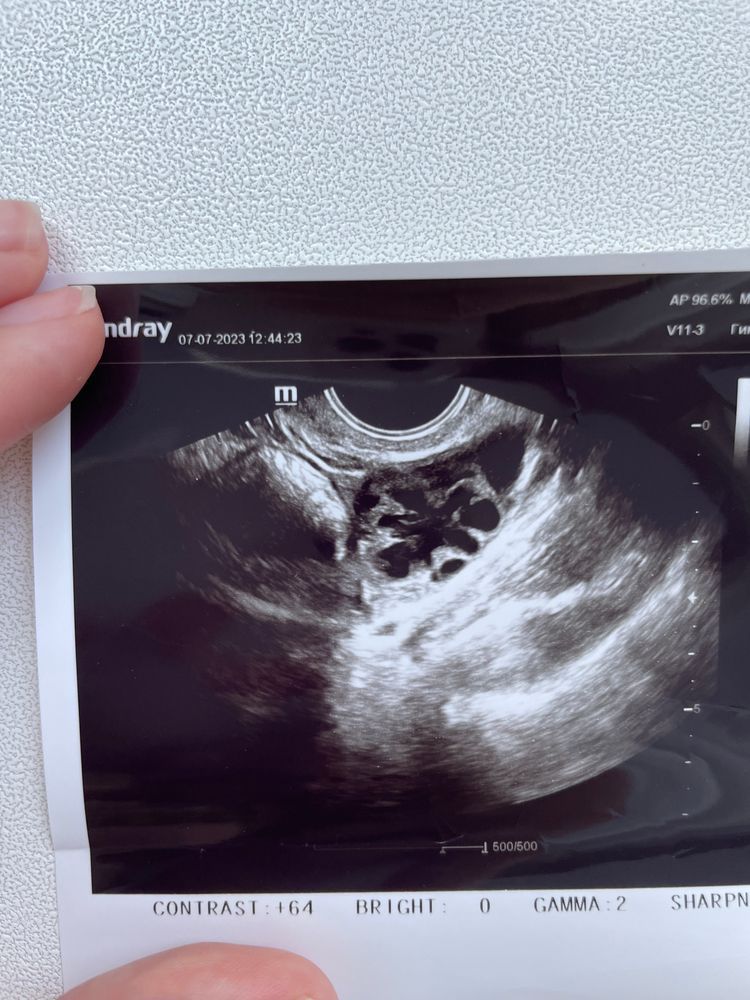

купила хгч укол 10000 ед. сходила к врачу , она мне сказала, будто бы есть желтое тело, и даже без укола хгч… (фото прикладываю, может кто то понимает)

На фото да, жёлтое тело